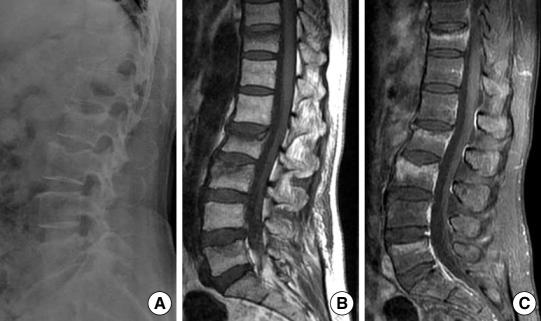

Although little attention has been paid to the less common rheumatoid involvement of the thoracic and lumbar regions, some studies have shown that rheumatoid synovitis with erosive changes can develop in these diarthrodial joints. We report a patient with seropositive rheumatoid arthritis (RA) involving the thoracic and lumbar vertebra with a collapse of the T12 vertebra, who was treated with percutaneous vertebroplasty. In this case of a painful pathological fracture due to RA, percutaneous vertebroplasty was found to be helpful in eliminating the pain. The paper presents the histological evidence, the pathogenesis and treatment of the thoracolumbar lesions affected by RA with a review of the relevant literature.

尽管人们对较少见的胸腰椎类风湿性受累关注较少,但一些研究表明,这些滑膜关节可出现侵蚀性变化的类风湿性滑膜炎。我们报告了 1 例血清阳性的类风湿关节炎(RA)患者,其胸腰椎受累,T12 椎体塌陷,采用经皮椎体成形术治疗。在这种由 RA 引起的疼痛性病理骨折的情况下,经皮椎体成形术有助于消除疼痛。本文通过复习相关文献,介绍了 RA 累及胸腰椎病变的组织学证据、发病机制和治疗方法。